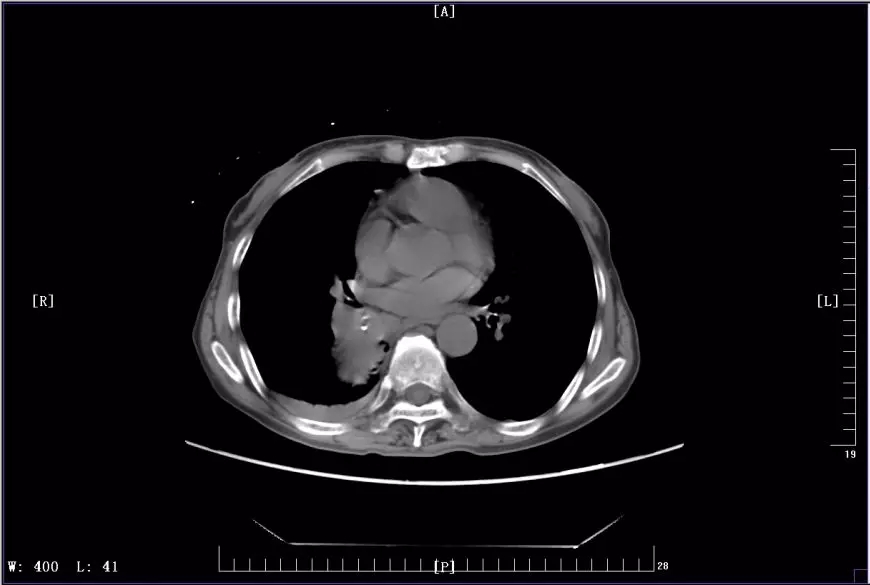

下图是徐丽参加KEYNOTE-407临床试验前后CT影像对比图:

2017年11月治疗前CT影像